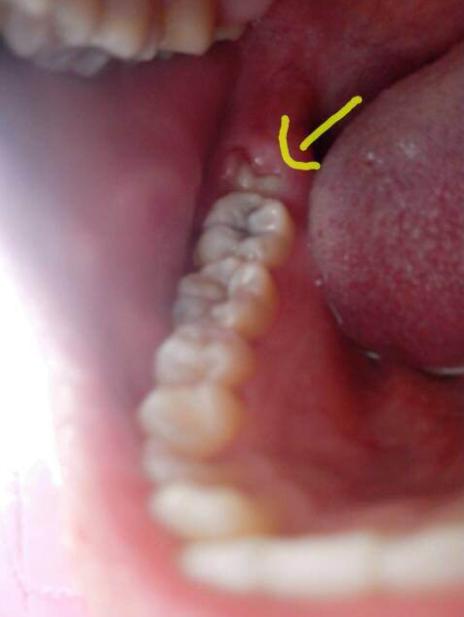

牙医经常在临床评估过程中诊断冠周炎。 牙医将通过检查智齿并检查体征和冠周炎的外观来诊断病情。

牙医将检查牙龈是否发炎,发红,肿胀或流脓。 他们还将寻找患处是否有口香糖瓣。